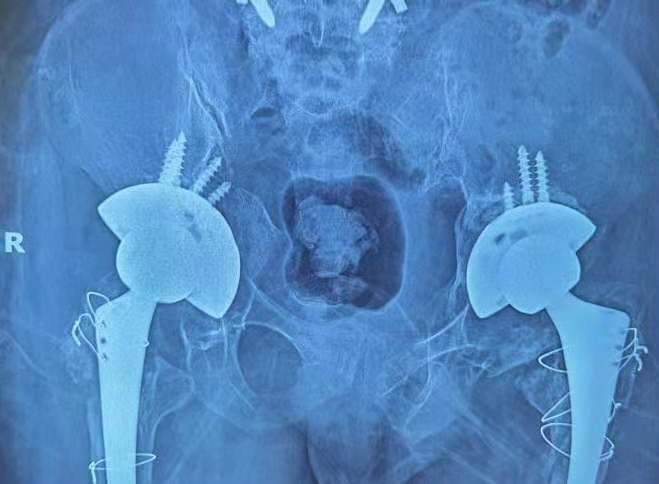

下图是患者术前术后X线的对比

术后X线: